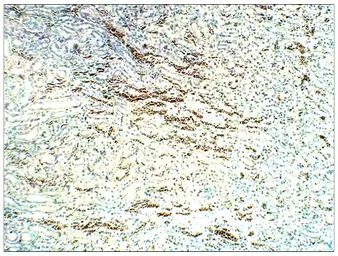

STRA6 antibody

Cat. No. GTX47858

ApplicationsWB IHC-P IP ELISA